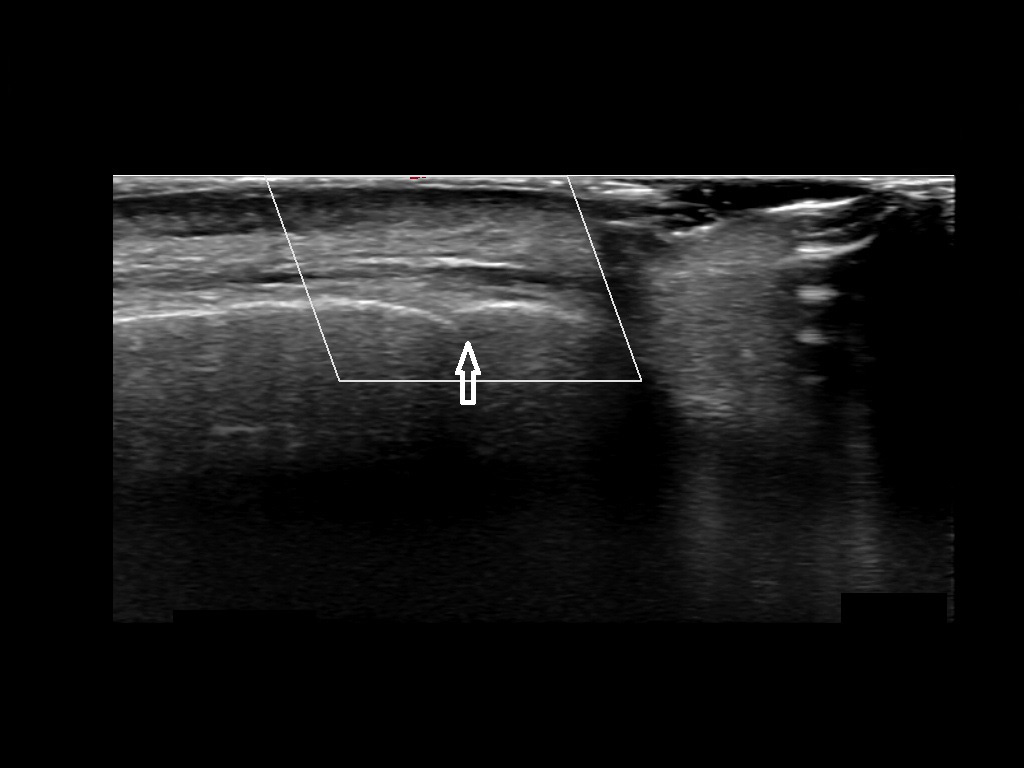

In this section you will learn more about the different layers of the face with the use of ultrasound. When you click on the secondary ultrasound image, you will see the different structures as an overlay. This will help to train yourself to recognize the different layers of the face.

Study the first image to recognize the different layers. If you are sure about the layers, swipe to the second image to view the answer (if applicable).